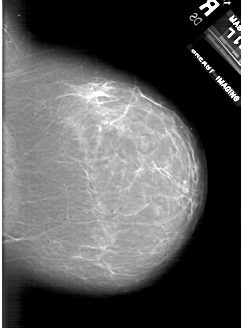

A_1818_1.RIGHT_MLO

RIGHT_MLO LINES 6871 PIXELS_PER_LINE 4816 BITS_PER_PIXEL 12 RESOLUTION 43.5 NON_OVERLAY